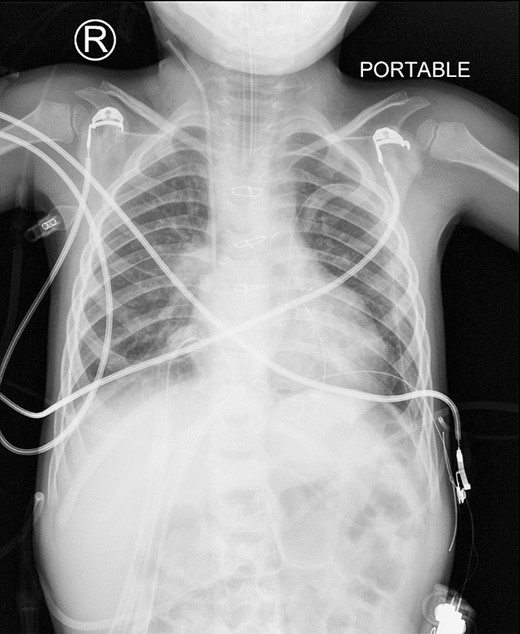

A preoperative assessment revealed an unexpected diaphragmatic hernia found incidentally on a routine chest X-ray (Fig. 1). This led to further tests, including a chest computed tomography (CT), which showed a central diaphragmatic defect with part of the transverse colon herniated into the chest (Fig. 2). Additionally, echocardiography found a perimembranous VSD with bidirectional shunting and mild tricuspid valve regurgitation. Cardiac catheterization confirmed reactive pulmonary vascular resistance.

This is a preoperative chest X-ray with an AP view revealing subtle lucent mediastinal structures in the lower mid-chest.

These CT chest scans in the coronal (A) and sagittal (B) planes, showing an anterior central diaphragmatic defect measuring 4.3 cm × 2.8 cm (TR × AP) with intrathoracic herniation of part of the transverse colon.